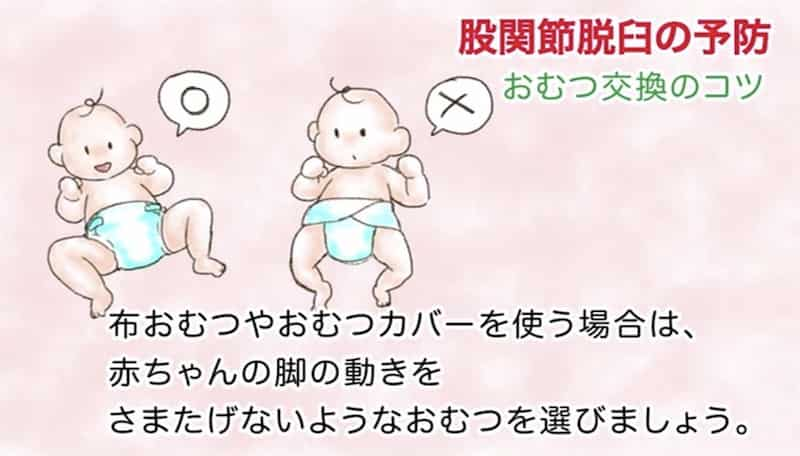

① おむつ

三角/巻おむつではなく股おむつを使って、脚が自由に動かせるようにしましょう。M字型に開けるようにして、伸ばされた状態で固定しないようにしましょう。股関節を開くために、二重おむつで無理やり開いて固定するのは逆効果です。

三角/巻おむつではなく股おむつを使って、脚が自由に動かせるようにしましょう。M字型に開けるようにして、伸ばされた状態で固定しないようにしましょう。股関節を開くために、二重おむつで無理やり開いて固定するのは逆効果です。

便漏れを防ぐために両サイドのテープの幅が広いものがありますが、これをきつく止めると股関節を伸ばした状態で固定されてしまうので、サイドテープの幅は狭いものを選び、きつく締めないようにしましょう。おむつ交換の時には、足先から持ち上げるのではなく、お尻の下に手を入れて持ち上げるようにしましょう。